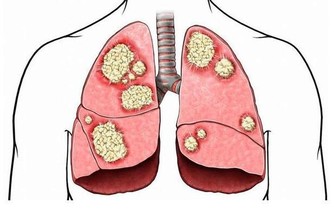

4 、肝怕“油”,多吃少動要不得

如果我們總是吃油膩的、高熱量的食物,也是非常損害肝臟的。大量未消化掉的油脂會增加血液中膽固醇、甘油三酯的濃度,也會在肝臟處積累,結果就是脂肪肝。而且,就算是有的朋友吃的油並不大,但是每天都不運動,肝臟也容易積累脂肪,所以在臨床上,我們經常看到瘦人到醫院一查也是脂肪肝。